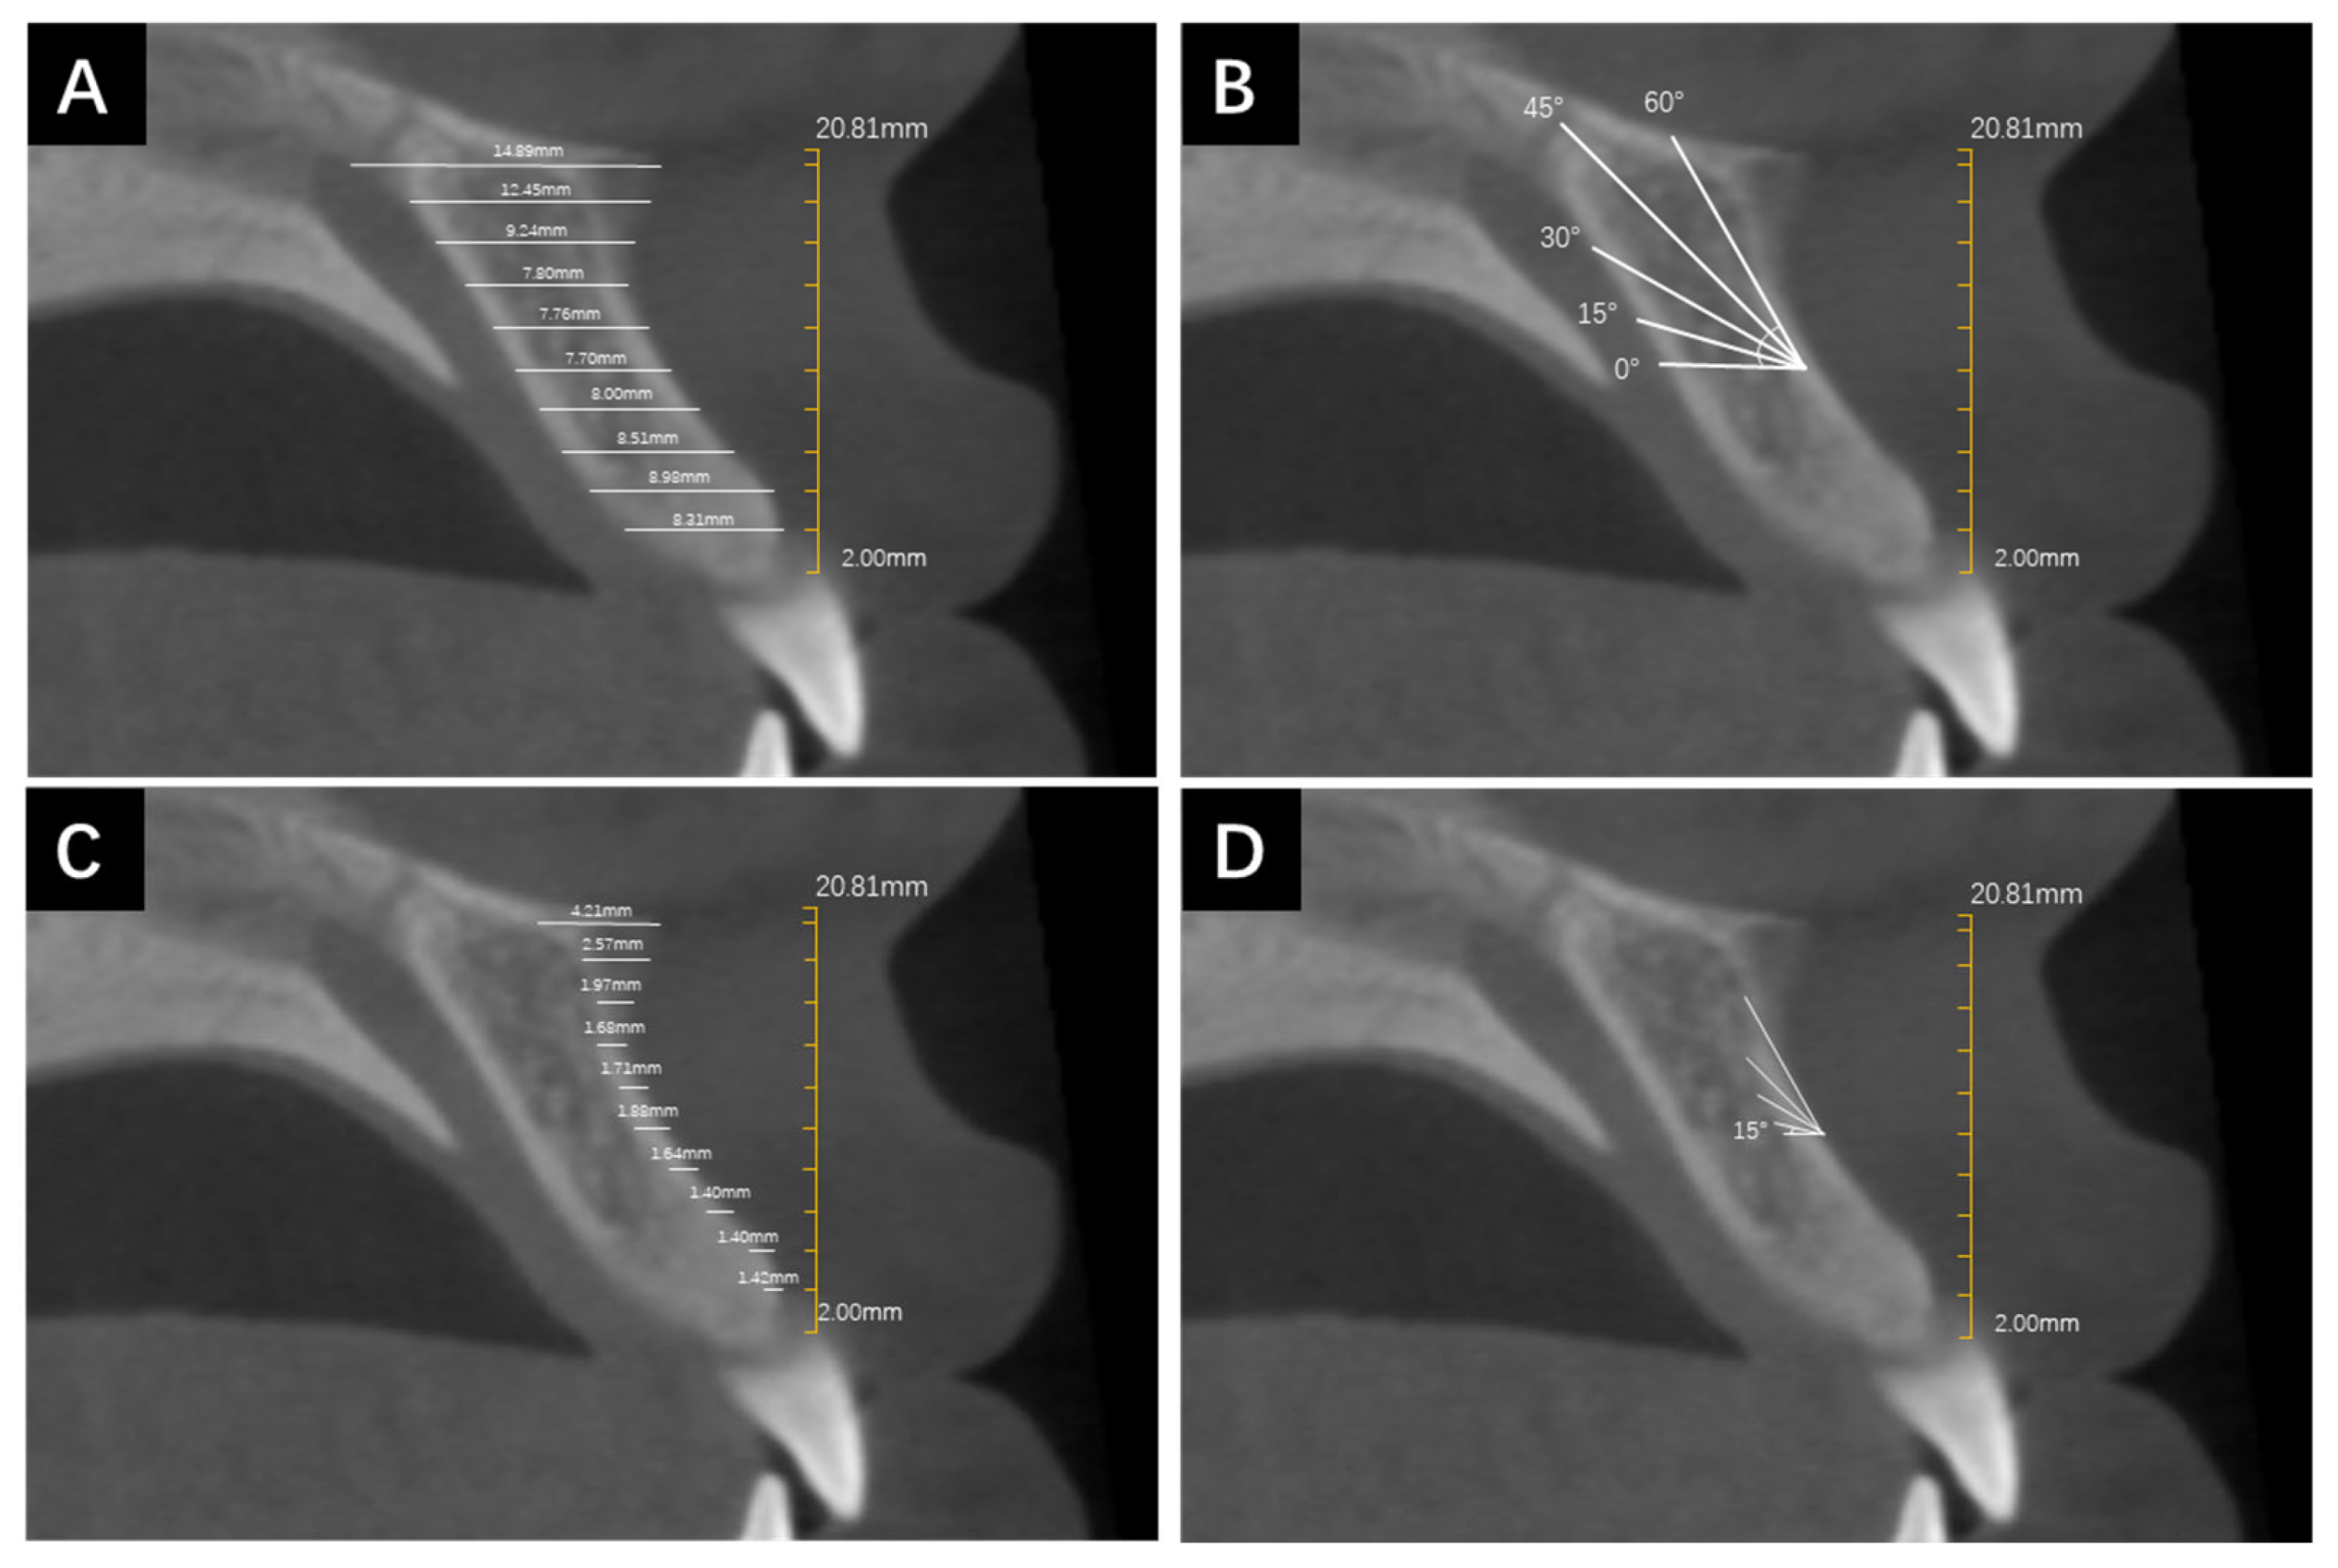

2. Materials and Methods

2.3. Measurement Protocol

3.2. Determine ANS Start

3.3. The Relationship between CBT and BD with Respect to Height Variations at 0°, 15°, 30°, 45°, and 60° Insertion Angles